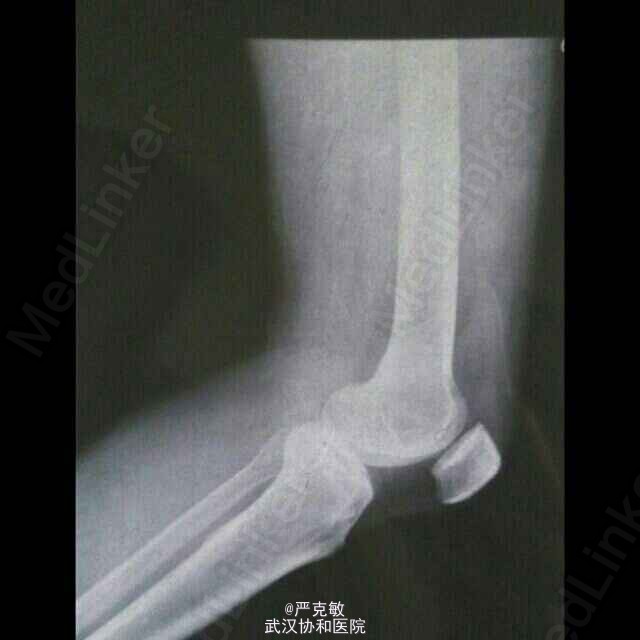

患者男,53岁。主诉:左侧膝关节疼痛一月,加重两天。病史:患者一月前劳动后出现左侧膝关节疼痛,休息后稍缓解,余无特殊不适,至当地诊所治疗(具体不详)三天未见明显好转,两天前疼痛加重,为求进一步诊治来我院就诊。

查体:左侧膝关节活动度减低,余未见明显异常。 辅查:左膝关节X片:左胫骨平台内侧髁间隆突骨质增生。

诊断:左侧胫骨骨质增生 治疗:给予复方氯唑沙宗胶囊、盐酸氨基葡萄糖及醋氯芬酸肠溶片口服,给予外用止痛膏药。